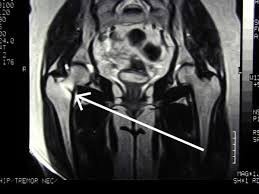

Medications for Stress Fractures You can take over-the-counter medications to manage pain. Initial treatment of a hip stress fracture may include X-rays a magnetic resonance imaging MRI scan or a bone scan to further evaluate your condition.

Coronal Mri T1w Image Showing The Stress Fracture As Linear Download Scientific Diagram